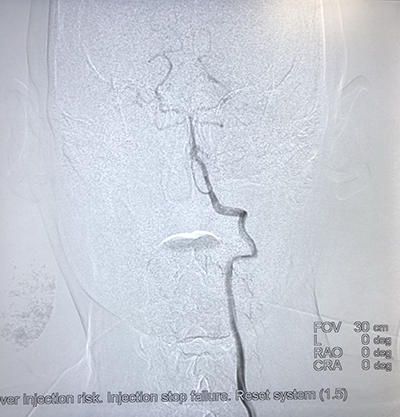

![]() | ![]() |

| (介入术中操作) | (肝癌的介入治疗) |